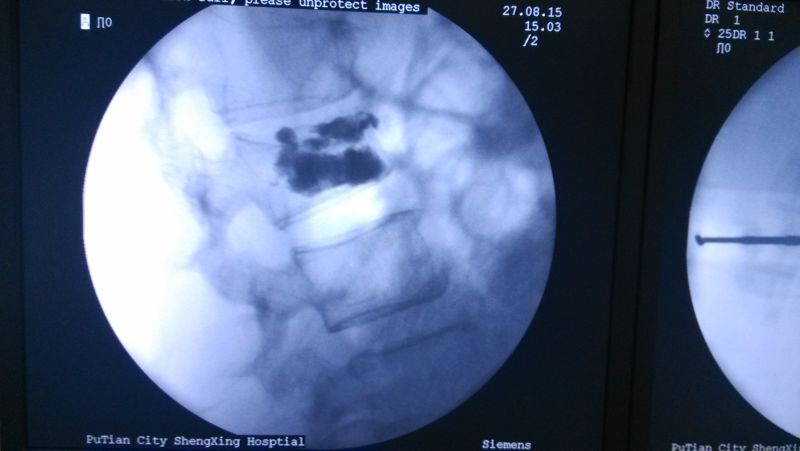

中醫(yī)科曹平主任組織全科醫(yī)生,對(duì)林阿婆的病情進(jìn)行討論、分析。認(rèn)為該病人可以采取“椎體成形術(shù)”進(jìn)行治療,精心制定了手術(shù)方案。8月27日,林阿婆被送入手術(shù)室,在林伯龍主治醫(yī)師的操作下,通過(guò)C型臂X光機(jī)透視定位,成功完成穿刺,并順利注入骨水泥。

術(shù)中透視

注射骨水泥